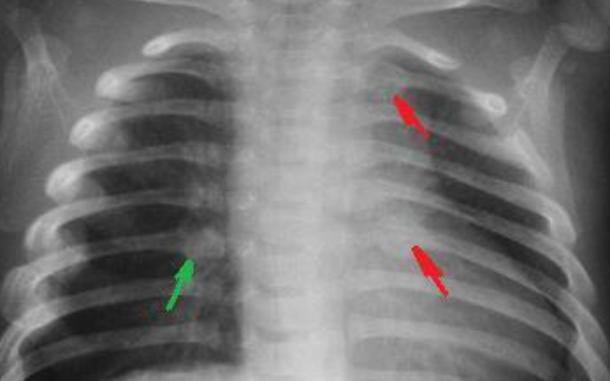

갈비뼈 금간 진단 방법

갈비뼈 금간 여부는 병원에서 다음과 같은 검사를 통해 진단합니다:

- 흉부 X-ray 촬영